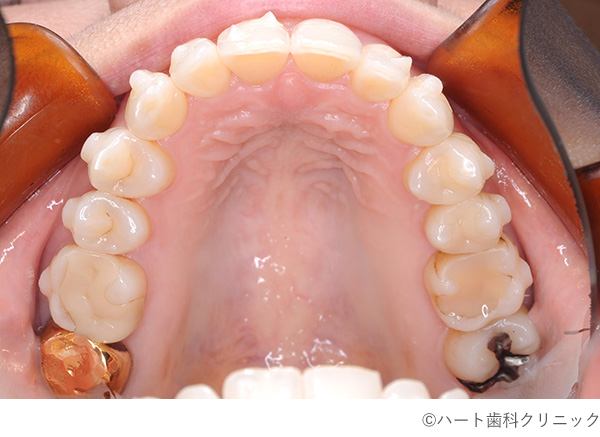

【症例】マウスピース矯正

- 治療前

- 治療後

- 治療名

- マウスピース矯正

- 費用

- 580,000円(税込)

- 期間

- 8ヵ月

- 通院頻度

- 1ヵ月ごと

治療内容

患者様の症状

下顎の歯のでこぼこ

治療法

-

下顎の拡大によるでこぼこの改善と、噛み合わせの調整の為に上の歯の移動を行いました。

また、歯と歯の間だを調整の為に少し削りました。 -

治療結果

気になっていた状態は改善されました。